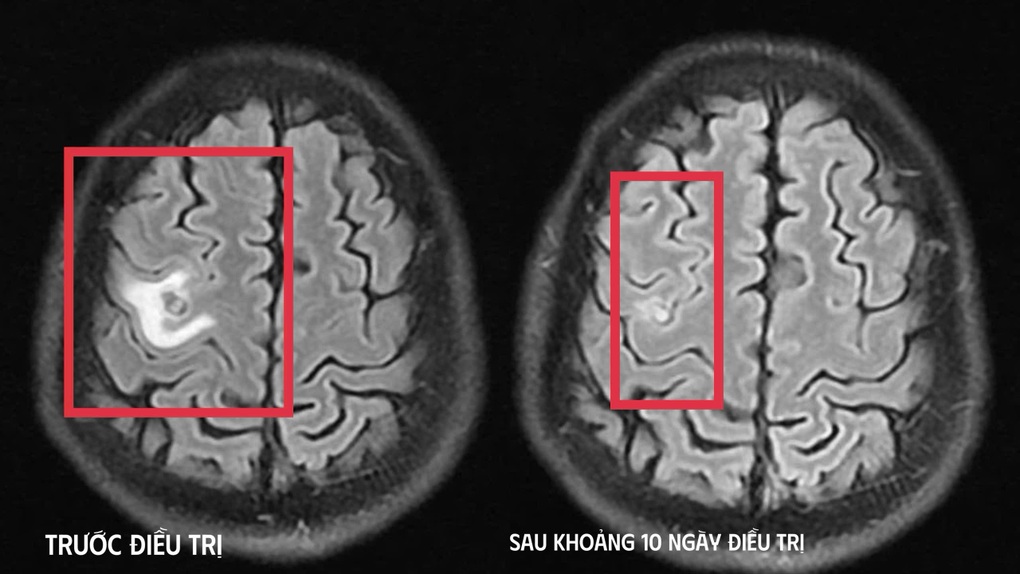

Hình ảnh chụp não bệnh nhân trước và sau điều trị (Ảnh: Bệnh viện cung cấp).

Bệnh nhân được chụp cộng hưởng từ (MRI) sọ não, phát hiện tổn thương dạng nang nhỏ tại thùy trán trái, kích thước khoảng 11x7mm, xung quanh có phù não nhẹ.

Sau khoảng 10 ngày điều trị nội trú, tình trạng bệnh nhân cải thiện rõ rệt, hết tê tay, không còn xuất hiện cơn co giật, không đau đầu hay chóng mặt, toàn trạng ổn định. Người bệnh được cho ra viện và tiếp tục điều trị ngoại trú đủ liệu trình kéo dài 4 tuần.

Khi tái khám gần một tháng sau, kết quả chụp cộng hưởng từ cho thấy tổn thương não thu nhỏ (cụ thể hình dạng nang) rõ rệt, phù não giảm, không còn dấu hiệu tiến triển, đáp ứng điều trị tốt. Bệnh nhân tiếp tục được chỉ định thêm một đợt thuốc củng cố và theo dõi lâu dài.